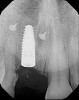

Prior to the initiation of the surgery, the surgical guide was tried in to confirm proper seating and stability (Figure 15). A flapless approach was not considered because the need for further bone grafting at the time of implant placement had been anticipated through the digital planning. A slightly palatal crestal incision was made, followed by two vertical incisions on the mesial and distal aspects of the edentulous site in order to preserve the papilla and avoid additional esthetic compromise to the anterior sextant. Next, a full-thickness flap was elevated to facilitate removal of the tenting screw and permit visualization of the buccal plate (Figure 16). A standard guided protocol was followed to place the implant, and its final position mirrored that of the digital plan. As predicted, the prosthetically driven implant position resulted in an insufficient buccal plate (Figure 17); therefore, additional guided bone regeneration was performed to reinforce the area and prevent future breakdown (Figure 18 and Figure 19). Making periosteal incisions could have compromised the blood supply to the flap, so instead, it was stretched in order to achieve tension free coronal advancement.31The flap was secured utilizing horizontal mattress sutures with additional supportive interrupted sutures to ensure primary closure (Figure 20). An immediate postoperative periapical radiograph (Figure 21) and CBCT scan (Figure 22) were taken, demonstrating a final implant position centered with the planned location of the gingival zenith.

(21.) Postoperative periapical radiograph taken immediately after placement of the implant at site No. 8 demonstrating implant positioning centered with the planned location of the gingival zenith and two titanium alloy tacks that were used to stabilize the resorbable membrane apically.

Figure 21